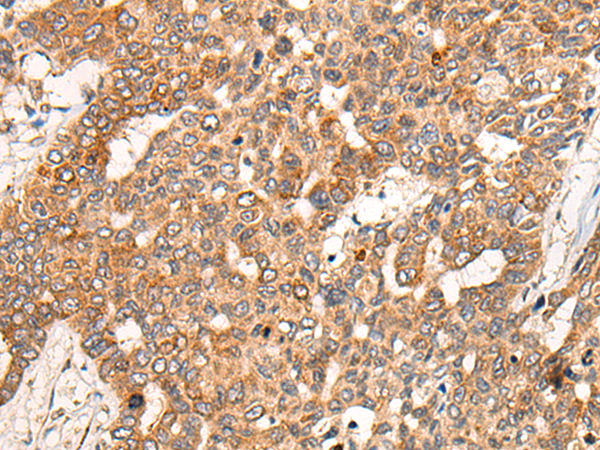

分类: 科研抗体货号: P09492别名: CGR11应用: IHC反应种属: Human